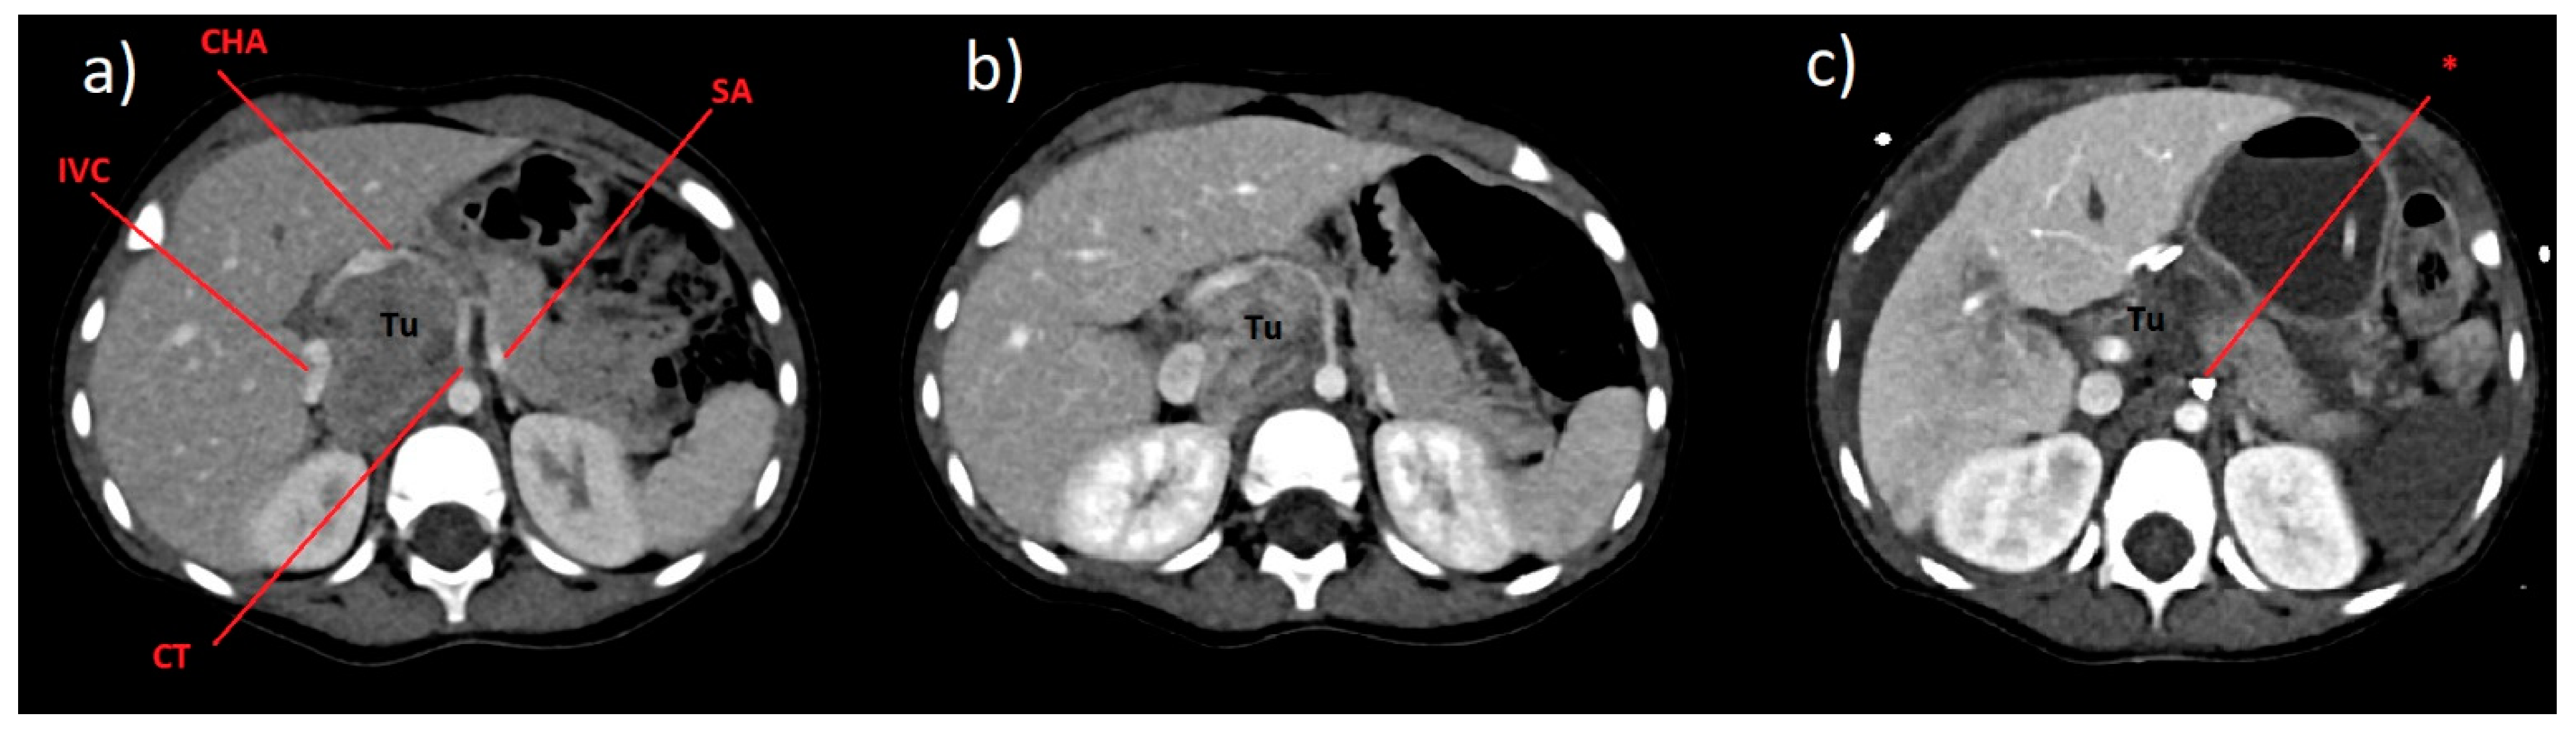

| 1 | 0 | Doppler USG CT | Neuroblastoma | Laparotomy, non-radical resection of the tumor, drainage of the peritoneal cavity, with accidental ligation of the visceral trunk |